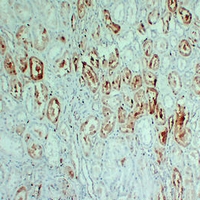

Immunohistochemical analysis of S100-A1 staining in human kidney formalin fixed paraffin embedded tissue section. The section was pre-treated using heat mediated antigen retrieval with sodium citrate buffer (pH 6.0). The section was then incubated with the antibody at room temperature and detected using an HRP conjugated compact polymer system. DAB was used as the chromogen. The section was then counterstained with haematoxylin and mounted with DPX. -